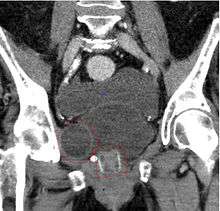

The procedure of choice for stress urinary incontinence in females is what is called a sling procedure. A sling implant usually consists of a synthetic mesh material in the shape of a narrow ribbon but sometimes a biomaterial (bovine or porcine) or the patients own tissue that is placed under the urethra through one vaginal incision and two small abdominal incisions. The idea is to replace the deficient pelvic floor muscles and provide a backboard of support under the urethra. Transvaginal mesh has recently come under scrutiny, as patients allege long-term harm and suffering as a result of implanted mesh.[14]

Transobturator tape

The transobturator tape (TOT or Monarc) sling procedure aims to eliminate stress urinary incontinence by providing support under the urethra. The minimally-invasive procedure eliminates retropubic needle passage and involves inserting a mesh tape under the urethra through three small incisions in the groin area.[17]